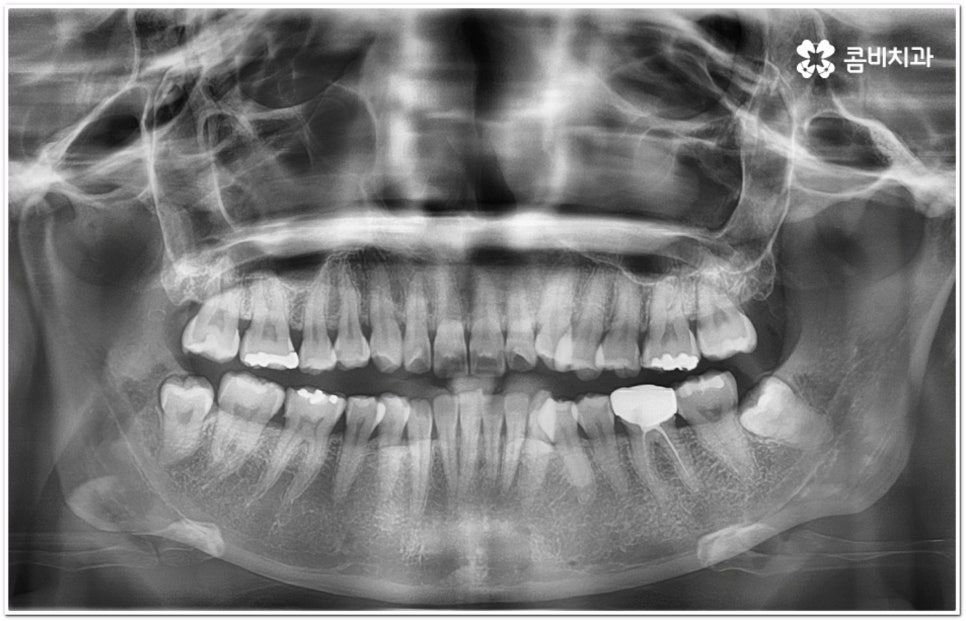

환자마다 치열, 교합, 치아가 튀어나온 각도, 잇몸이 드러나는 정도, 상악과 하악의 구조 및 관계 등 턱관절 관련 부분 상황이 모두 다르기 때문에 3D CT 같은 정밀 검진 기계를 통해 이를 꼼꼼하게 살펴보고 각각에 맞는 계획을 세밀하게 세워 교정 치료를 진행해 줄 필요가 있어요. 이때 환자분들의 상황에 따라 양악수술과 같은 외과적인 방법을 병행해야 하는 케이스도 있을 수 있기 때문에 돌출입을 가지고 계신 분들 중에서 수술에 부담을 느끼고 지레 치료를 포기하신 분들도 있을 수 있는데 정도가 많이 심각하지 않고 구조적인 원인이 크지 않다면 대부분의 케이스는 치아교정 만으로도 충분히 개선이 가능하니 먼저 돌출입교정치과 에 들러서 정밀 검사를 진행한 후 치료 방향에 대해 의료진과 논의해 보시면 좋을 거예요.